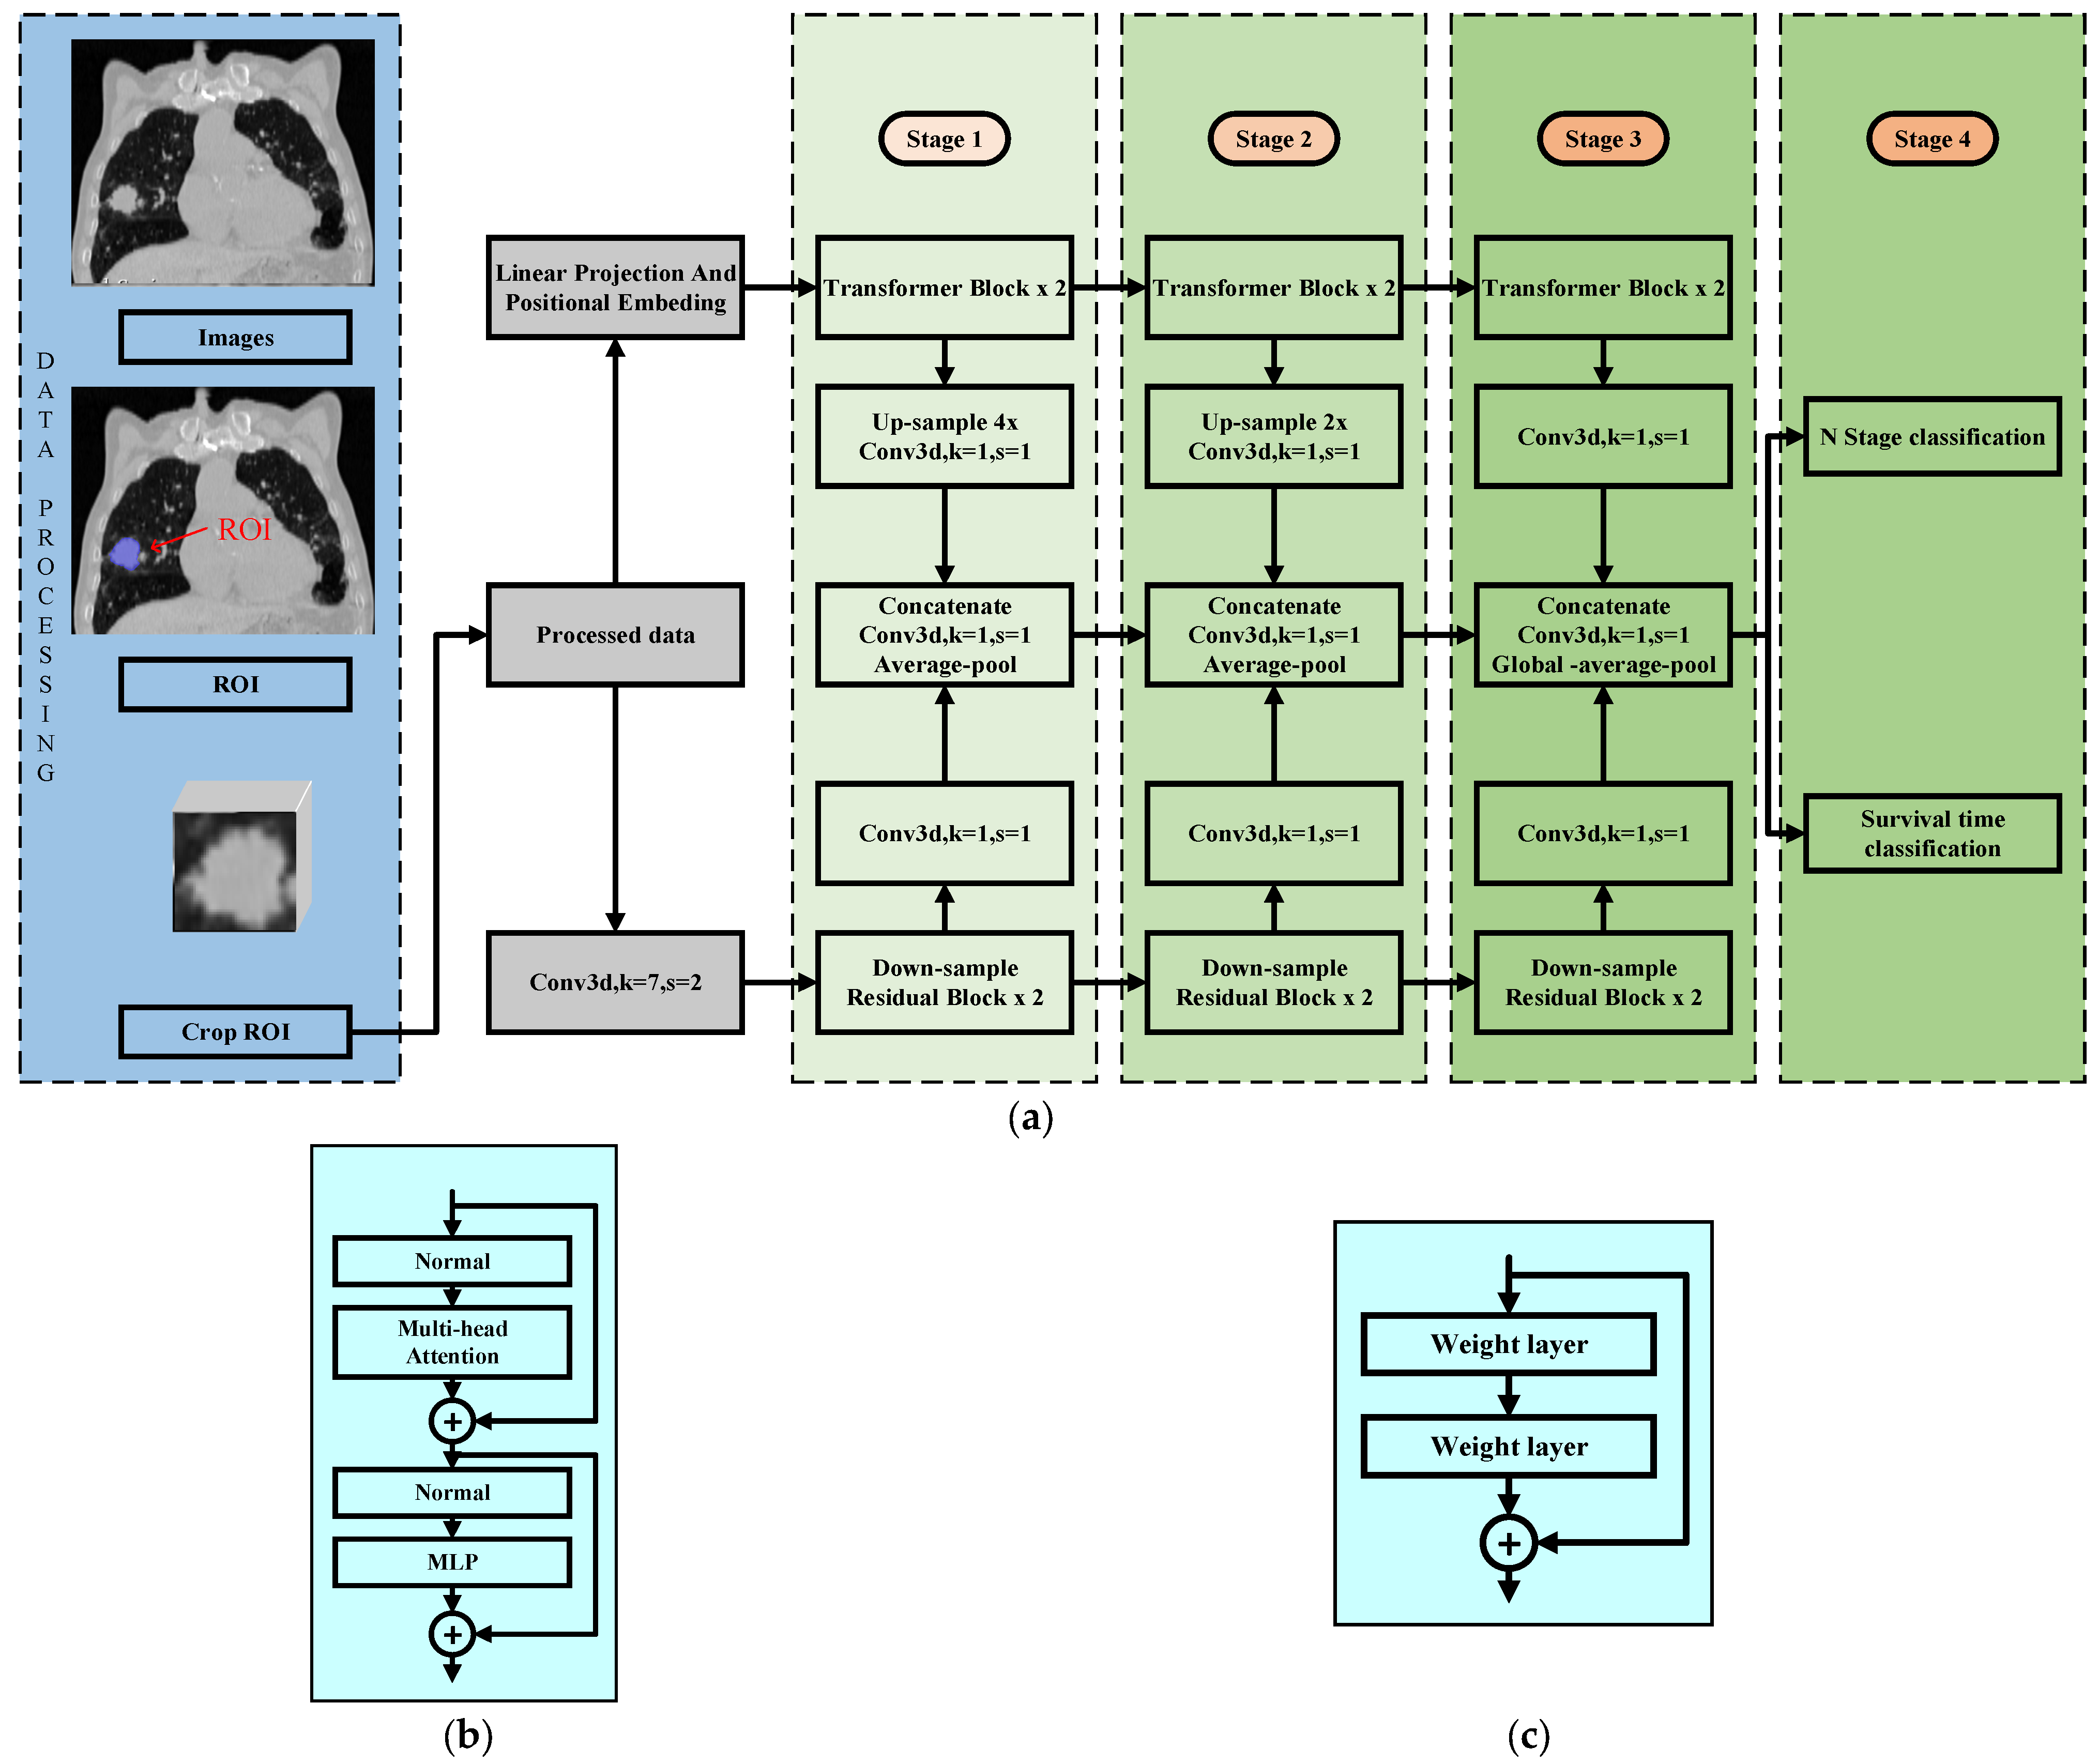

2. Model Description